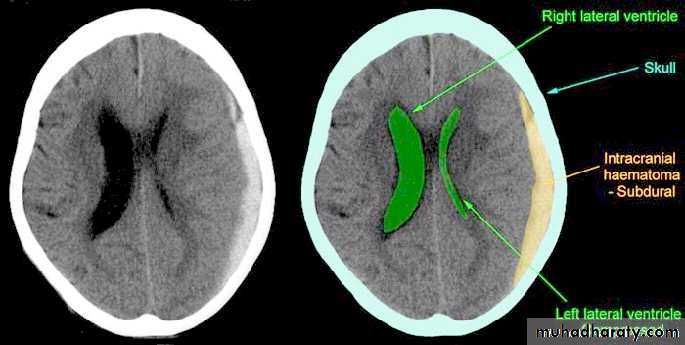

b. Subdural Haematoma

They are the most common intracranial mass lesions resulting from head trauma.

They are classified depending on how long they take to present clinically following the injury into:

Acute Subdural Haematoma: less than 3 days

Subacute Subdural Haematoma: 4-21 days

Chronic Subdural Haematoma more than 21 days.

Acute Subdural Haematoma

Clinical Picture: patient will present with a picture similar to that of an extradural haematoma, but there is persistent loss of consciousness with no lucid interval.

Ct scan will show a concave hyperdence collection because blood follows the subdural space over the convexity of the brain.

Acute Subdural Haematoma are rapidly evolving lesions and early evacuation via craniotomy is mandatory.